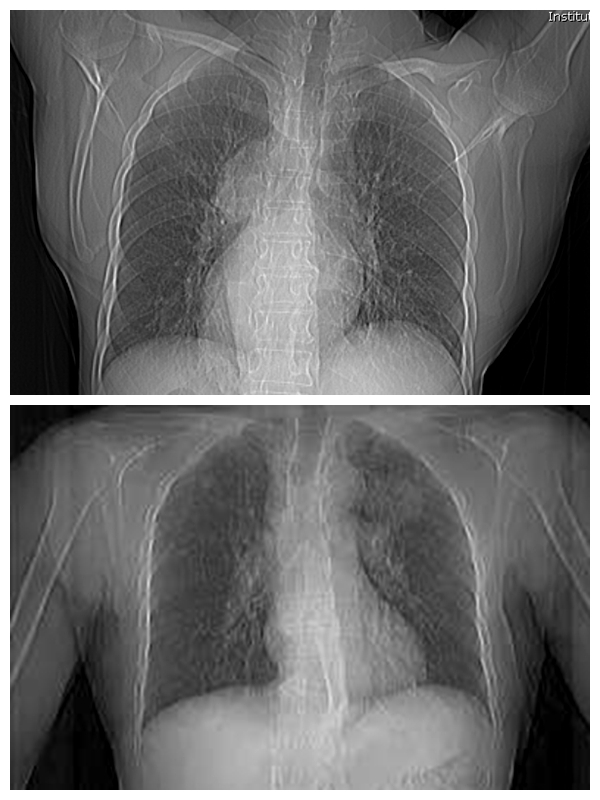

近日,62岁的黄大爷因左侧胸痛去医院体检,心电图提示异常。经过进一步检查后发现,黄大爷的内脏全部“长反”了,是罕见的“镜面人”。3月上旬,湘雅常德医院心胸外科为黄大爷完成肺部肿物切...